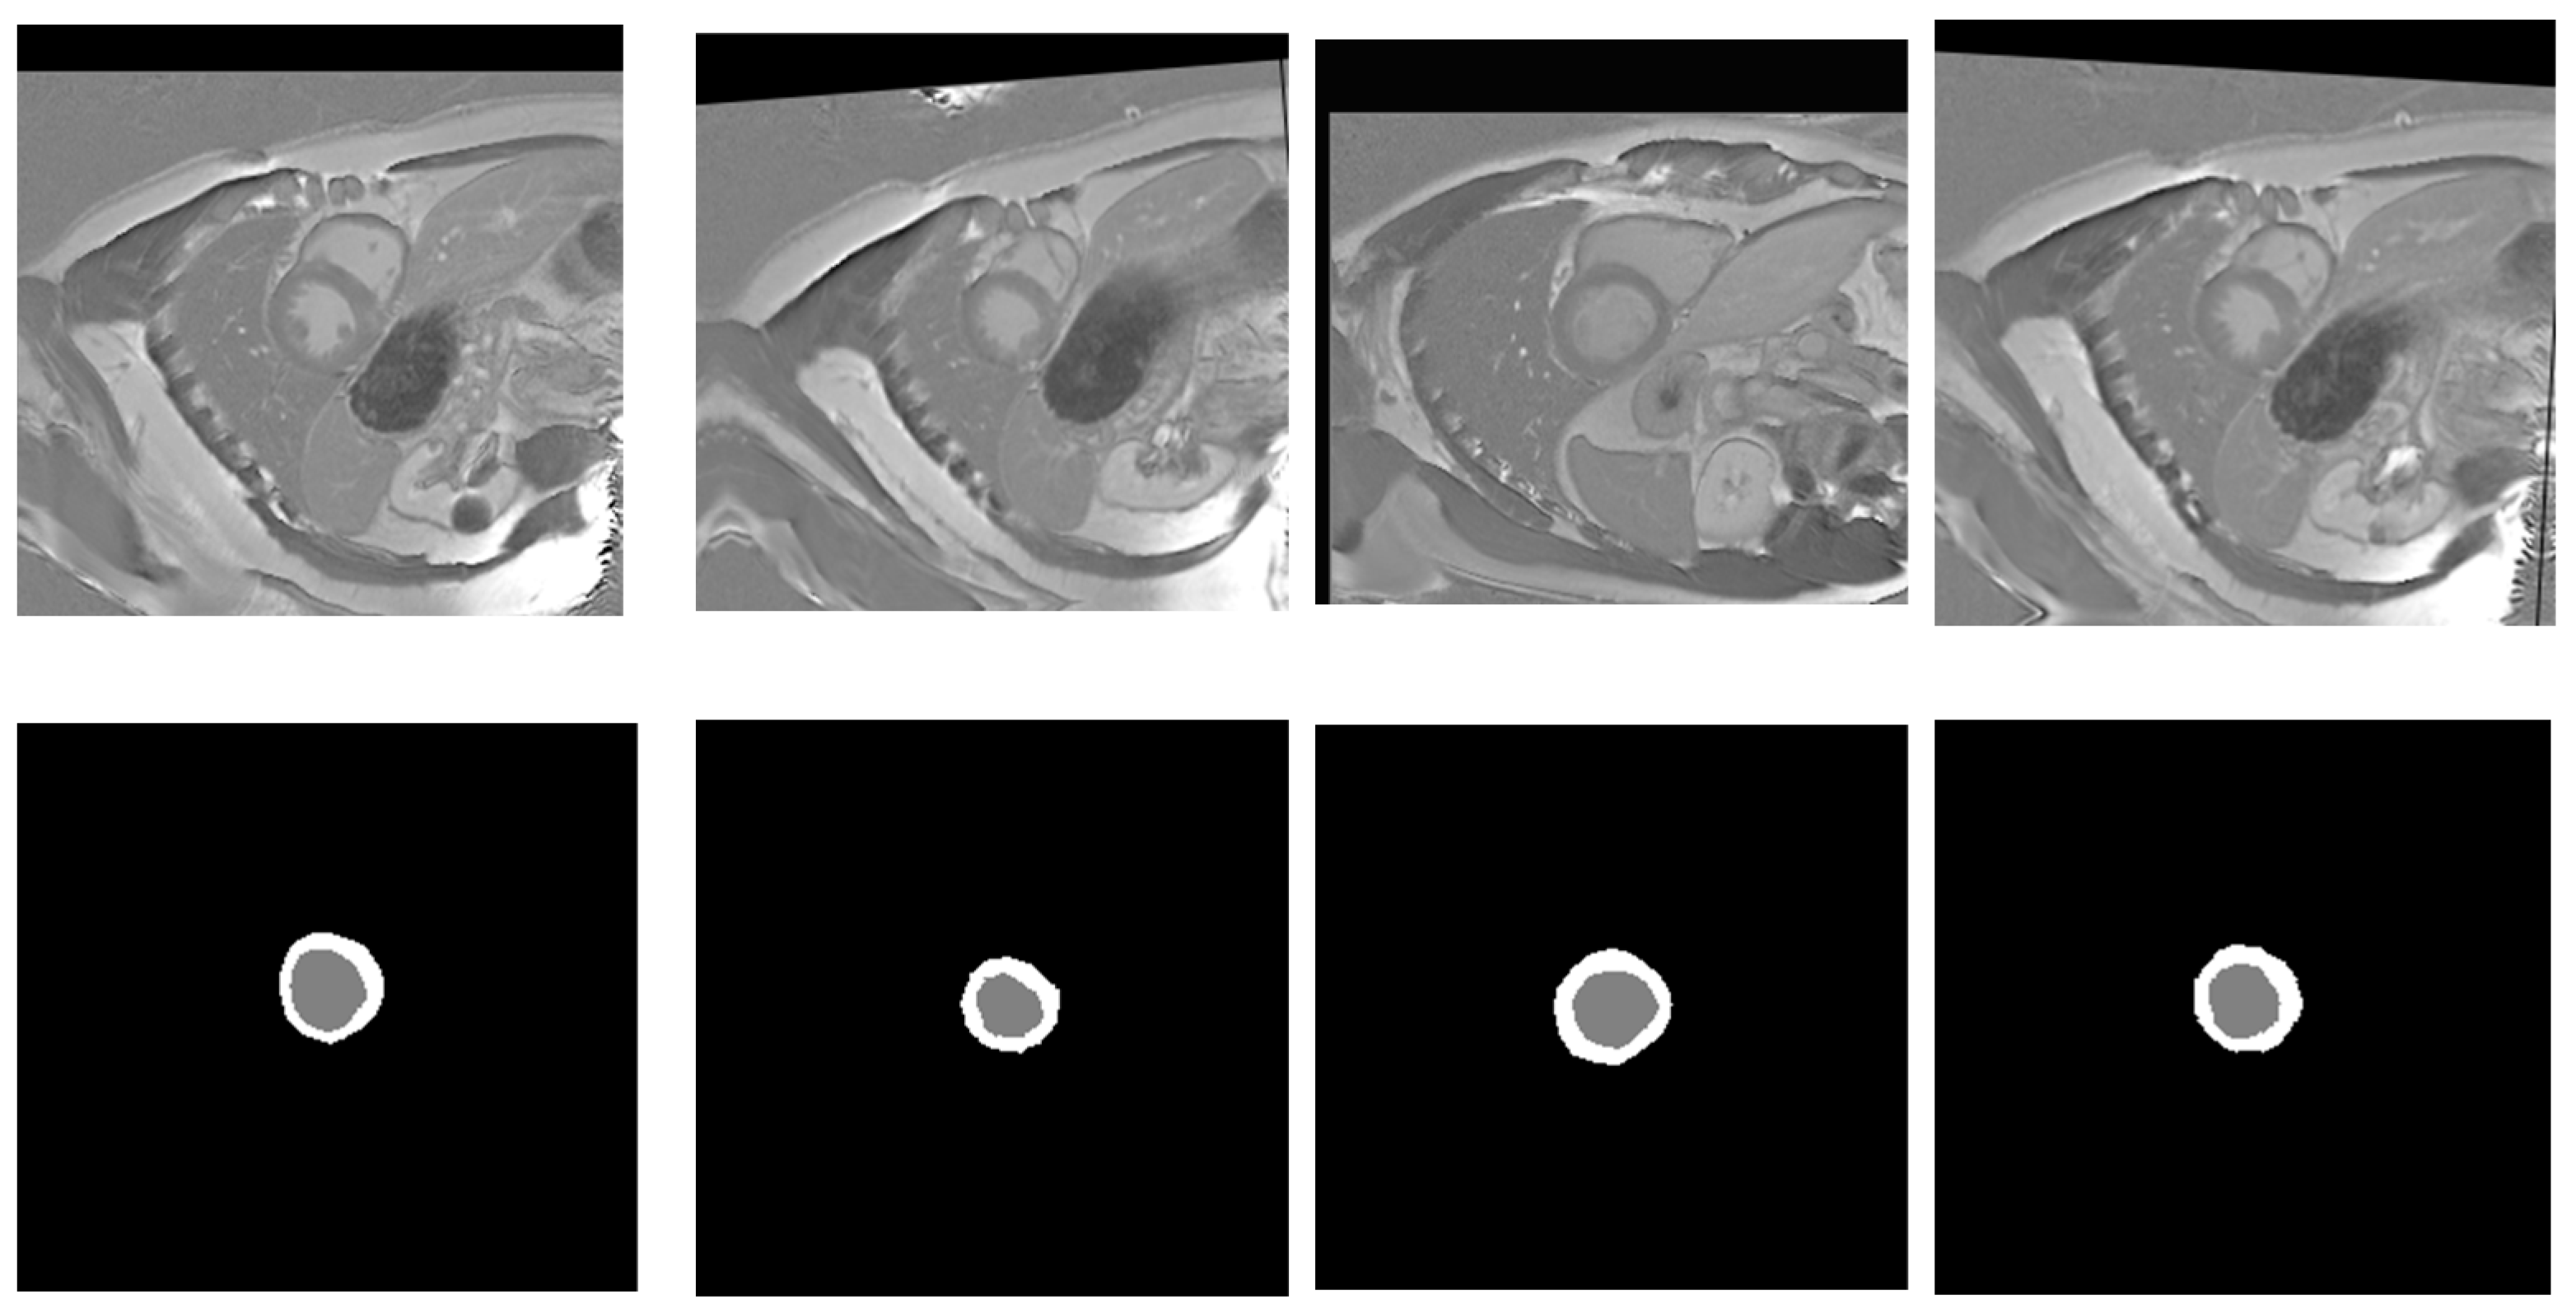

3.1. Datasets Description

3.1.1. EMIDEC 2020

3.2. Pre-Processing

3.2.1. Cardiac MRI Enhancement

3.2.2. Cardiac MRI Augmentation